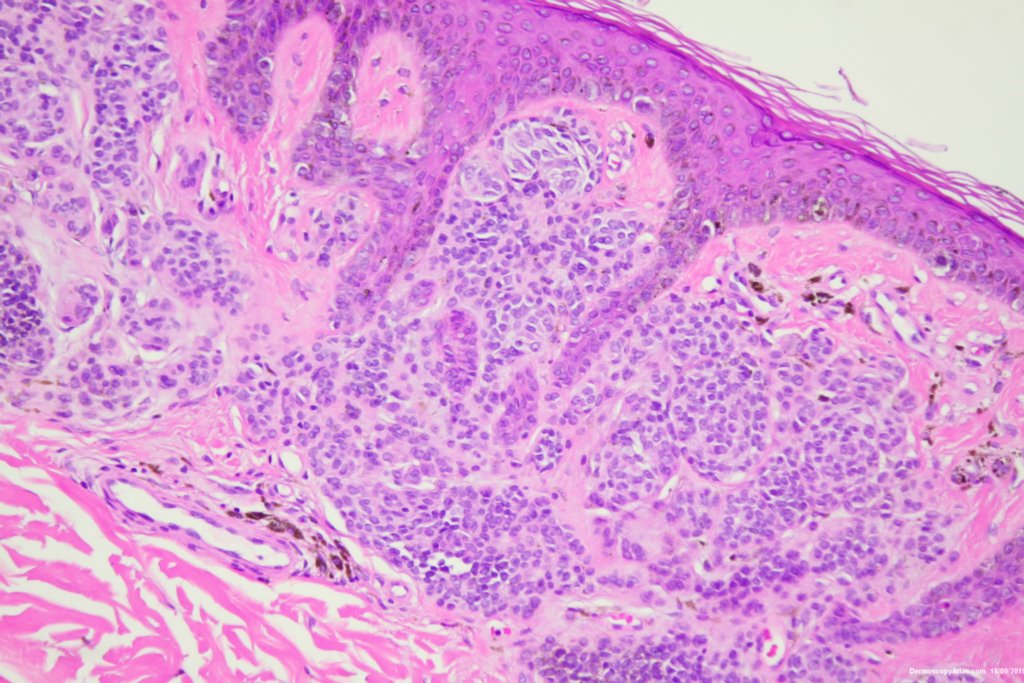

Description: Some grey dots and thickened network

A pigmented lesion on the ankle which showed some grey dots suggesting regression and a slightly thickened network in parts.

Histology showed a compound nevus with some pigment in melanophages in the dermis giving the grey.